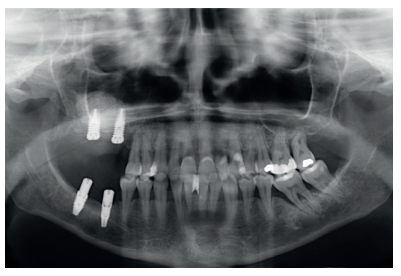

This was the case of a 58-year-old female patient who attended the dentist practice to assess the 16th and 17th molars for pain and mobility. On clinical examination, mobility of both was observed with suppuration at the level of the sulcus. Radiography confirmed our diagnosis of considerable bone loss and sinus perforation at the apex of both molars (Figure 2).

Back in 2007, the therapeutic protocol for these cases was very different (Figures 5-7), with short implants without full development – and without studies demonstrating the importance of diameter over implant length – efforts were focused on the search for anchorage by implant length instead of looking for the bicortical (vestibular-lingual) stability that short and wide implants perform. During this time, the failure of molars 46 and 47 also occurred; these were also extracted and replaced with dental implants.